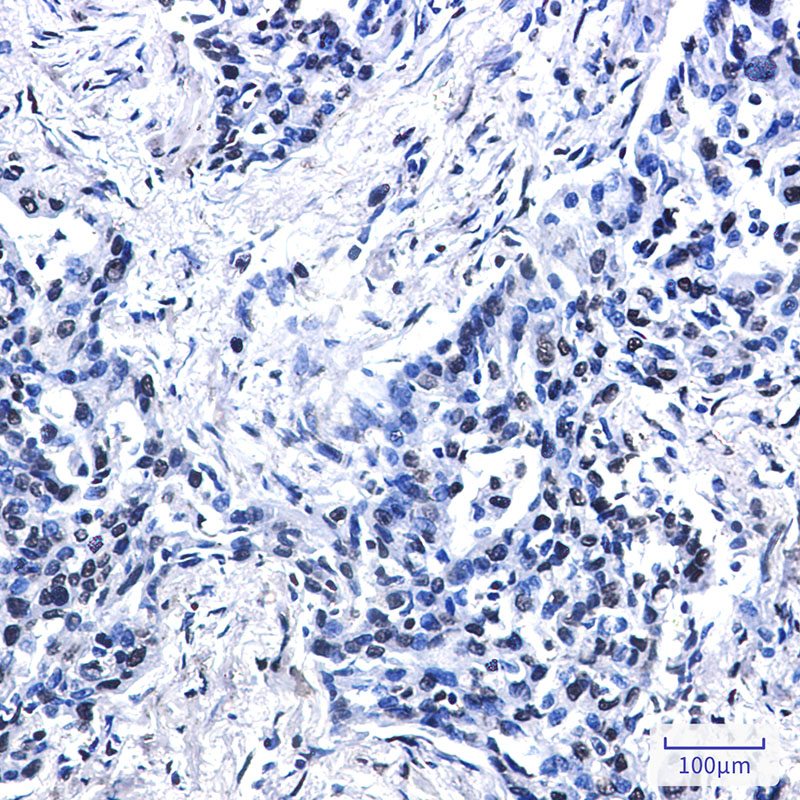

Dilution | WB~~1/500-1/1000 IHC-P~~N/A IHC-F~~N/A IP~~N/A ICC~~N/A |